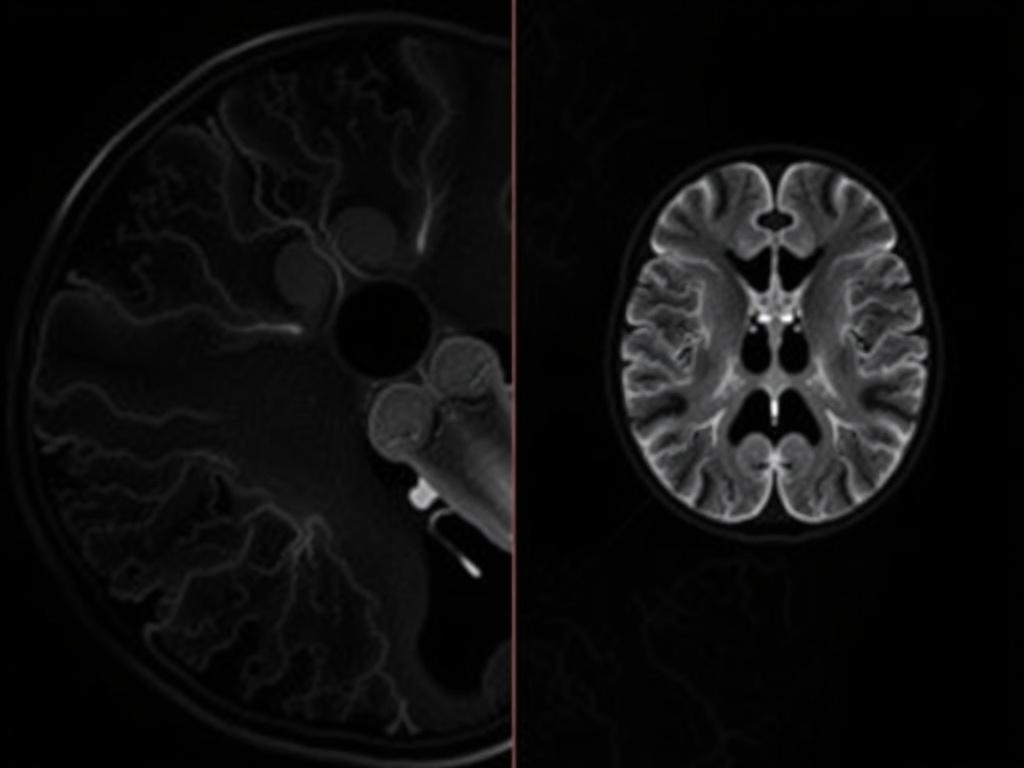

МРТ-ангиография, или МРА, — это разновидность магнитно-резонансной томографии, ориентированная на визуализацию сосудов. Обычная МРТ показывает ткани и органы, а МРА — тонкую сеть артерий и вен в высоком контрасте. Разница кроется не в аппарате, а в программировании последовательностей и способах обработки изображений. На сайте https://eurodicenter.ru/uslugi/magnitno-rezonansnaya-tomografiya/magnitno-rezonansnaya-tomografiya-sosudov/magnitno-rezonansnaya-tomografiya-angiografiya можно получить больше информации про МРТ-ангиографию.

В основе лежат свойства крови: движущаяся кровь по-разному реагирует на радиочастотные импульсы и градиенты поля по сравнению со статическими тканями. Выбирая нужную последовательность, техник делает сосуды яркими, а окружающие ткани — приглушёнными, что и дает понятную карту сосудистой сети.

Сигнал от крови можно выделять по скорости, по фазе или по времени пролета. Кроме того, современные томографы умеют снимать трёхмерные объёмы с высокой разрешающей способностью, а затем реконструировать их в виде максимальной интенсивности (MIP) или объемных моделей (VR). Такие изображения легко интерпретировать и удобно показывать пациенту.

TOF — один из самых распространённых неинвазивных методов. Его идея проста: свежая кровь, входящая в зону сканирования, еще не облучалась предыдущими импульсами и дает яркий сигнал. Статические ткани «затемнены», поэтому сосуды выделяются контрастно.

TOF хорош для сосудов головного мозга и шеи, но чувствителен к очень медленному току и турбулентности — там сосуд может выглядеть суженным или вовсе исчезнуть. Для оценки динамики кровотока этот способ ограничен.

После сканирования DICOM-объём обрабатывают: строят MIP-снимки, объёмные реконструкции и срезы по кривой плоскости. MIP показывает максимальное значение сигнала вдоль проекции и часто используется для быстрой оценки анатомии. VR даёт объёмную модель, удобную для планирования операции или эндоваскулярного вмешательства.